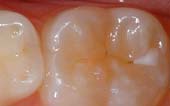

Seal Out Decay

A sealant is a protective coating that is applied to the chewing surfaces (grooves) of the back teeth (premolars and molars), where four out of five cavities in children are found. This sealant acts as a barrier to food, plaque and acid, thus protecting the decay-prone areas of the teeth.

Before

Sealant Applied

After